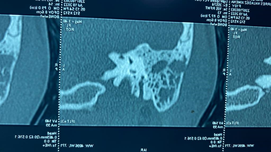

Se realiza tomografía computarizada simple de oídos donde se observa en oído derecho conducto auditivo externo ocupado en su tercio medio por lesión isodensa a hueso, de 8.54 x 8.65 mm, redonda, pediculada de origen en pared anterior, de bordes regulares, sin remodelación ósea, con presencia de material isodenso a tejidos blandos periférico a la lesión, sugestivo de cerumen; oído contralateral sin alteraciones. (Figura 2). Se realizó una audiometría tonal prequirúrgica (Figura 3, 4).

|

| (Figura 2) Lesión osea pediculada isodensa a hueso en CAE derecho. |

El colesteatoma del conducto auditivo externo se observa en la Tomografía computarizada simple de oído como una lesión con densidad a tejidos blandos en el CAE con erosión ósea asociada y fragmentos óseos intralesionales (Figura 6). La erosión ósea adyacente a la lesión de tejido blando puede ser lisa, similar a un colesteatoma del oído medio; sin embargo, la erosión puede ser irregular debido al hueso necrótico y la periostitis. Por lo general, las paredes inferior y/o posterior están involucradas. Es importante evaluar la extensión hacia la cavidad del oído medio y la integridad del canal del nervio facial, tegmen timpánico y celdillas mastoideas, ya que estas características pueden cambiar el manejo quirúrgico. Es importante destacar que, aunque la resonancia magnética es ampliamente utilizada en la evaluación de enfermedades del oído interno y medio, su utilidad en el diagnóstico de colesteatoma del conducto auditivo externo es limitada. La secuencia de difusión puede llegar a ser de utilidad para la realización de diagnósticos diferenciales con otras lesiones del CAE.

(Figura 6). Corte coronal. Muestra un CCAE como una lesión submucosa erosiva y dentada en el CAE óseo inferior.

Se observa erosión ósea con fragmentos óseos dentro de la matriz del colesteatoma.